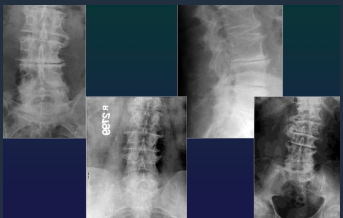

Spondylolisthesis + Spondylolysis

Spine

AS Dg recommendations

Early: MRI (detect early infection)

Late / advanced: Rx

Sacroilic Rx= business card of AS patient

Complication or trauma: CT, MRI

Spine AS

Shiny corners

Square vertebrae

Syndesmophites

Bamboo stick

Calcifications

Interspinate

Yellow lig (tram line)

Sacroiliitis AS

Bilat, symmetrical

Subchondral OS

Erosions + false widening

Bone bridges, narrowing

Fusion : ankylosis

ARA Dg criteria AS

Lumbar pain > 3 maths, NOT eased by resting

Pain + stiffness in chest

Limmited breathing movements

Limited spinal mobility

Iritis

Sacroileitis Rx

Syndesmophytes Rx

AS Dg

Dg: syndesmophyes + bilat sacroilitis

LOC

SI joints (synovial part inf 1/2-1/3)

Large proximal joints : hips, shoulder

Spine (DL)

Anterior margins

Anterior fibers of fibrous ring

AS

Inflammatory arthropathy & enthesopathy located mainly in the axial skeleton

HLA-B27

Incidence: 0,1 % pop (15-30 y) - B:F = 2,5-5 : 1